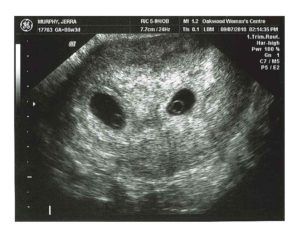

При одноплодной беременности на снимке различают темное околоплодное яйцо, которое имеет четкие, ровные границы и круглую или овальную форму. Его размер – 10 мм.

В плодном яйце заметен крошечный эмбрион (2–3 мм). На снимке он представляет собой пятно, напоминающее креветку или запятую, более светлого цвета. Если присмотреться, на картинке заметен желточный мешок (более темное пятно размером 4–6 мм) и не до конца сформировавшийся кишечник без характерных извилин.